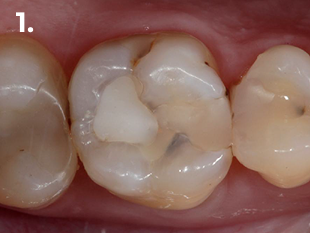

Fig. 1 Imagen Clínica Inicial

Paciente que acude a consulta refiriendo molestias en la zona del primer cuadrante. La exploración clínica y radiográfica reveló la presencia de una caries profunda distal, estableciéndose el diagnóstico pulpar de pulpitis reversible. Con el objetivo de lograr un adecuado punto de contacto tanto mesial como distal, se procedió a la eliminación completa de la restauración existente. El procedimiento se realizó bajo aislamiento absoluto, utilizando para el encofrado el sistema de matrices seccionales HALO. En la imagen clínica y radiográfica final se observan perfiles de emergencia bien conformados, convexos, así como puntos de contacto adecuados.